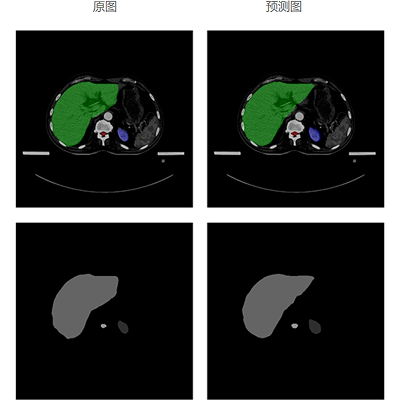

自动勾画效果

基于海量优选的专家勾画结构数据,利用深度学习人工智能技术,大力发展放疗智能勾画,自动勾画出精准且符合病人个性化特性的结果,帮助医生更加快速、准确地勾画肿瘤靶区和危及器官,从而推动放疗乃至肿瘤医疗的精准化、智能化发展,大大提高放疗勾画的工作效率。

模型经过对海量勾画结构数据的学习,以及改进优化,再进过大量样本数据训练及验证,自动勾画结果的平均准确度已达92%以上。